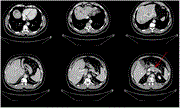

Unexpected long-term survival of Stage IV pancreatic cancer patient with synchronic liver metastases after multimodal therapy including upfront surgery

Aiman Obed and others

Journal of Surgical Case Reports, Volume 2023, Issue 1, January 2023, rjac638, https://doi.org/10.1093/jscr/rjac638